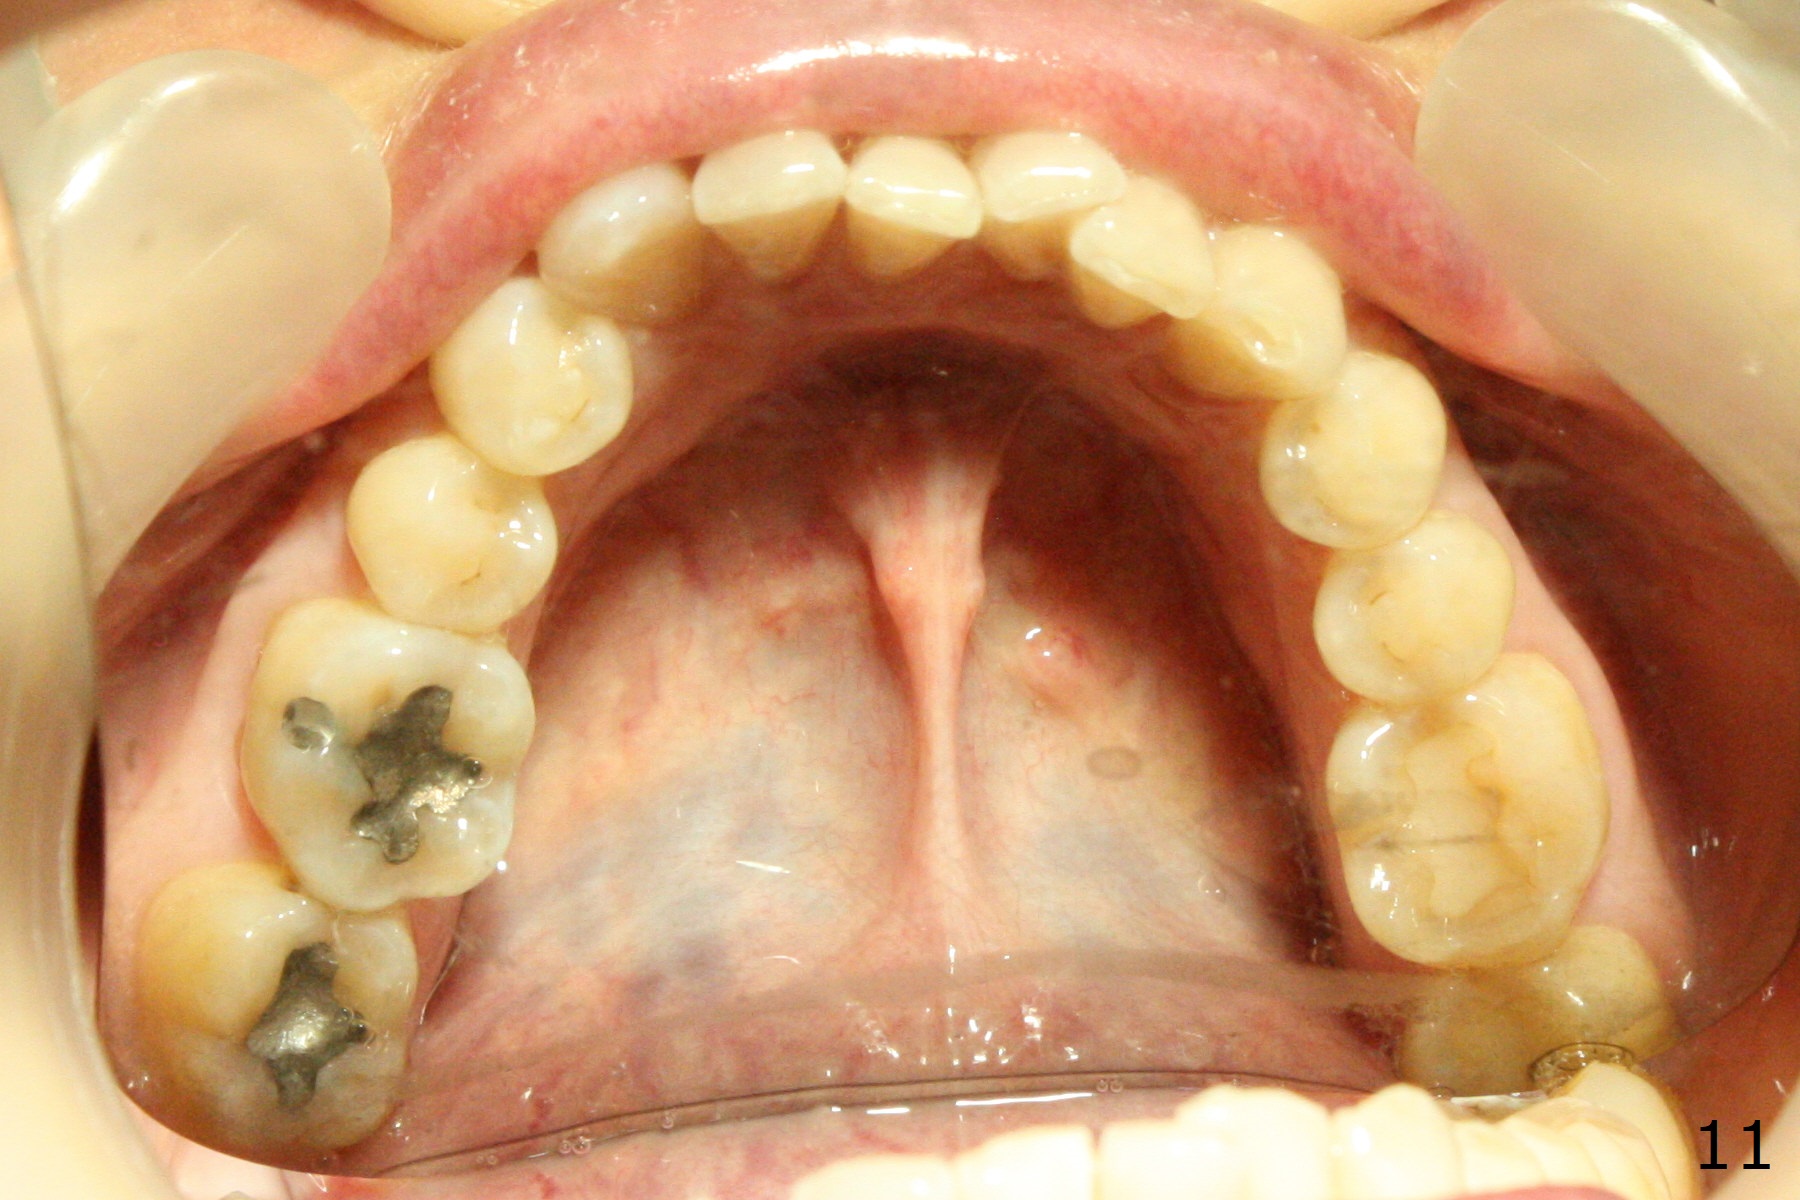

A 54-year-old woman (dento-phobic) will return for banding and bracketing 1.5 months post UR2 extraction with socket preser-vation. Lip strain is absent or minimal(Fig.1). The upper dental midline deviates to the right (Fig.2). Profile is within normal limit (Fig.3). UR3 is in cross bite (Fig.4). Cephalmetric X-ray apparently shows normal profile (Fig.5). Occlusion appears to be Class II in canine and molar (Fig.7,9, Class II Division II Malocclusion). The upper and lower dental midlines mismatch (Fig.8). UL2 is a peg lateral (Fig.10), while the lower anteriors are crowded (Fig.11). Arch wire sequence is conducted and let the timid patient decide whether the 2nd part of treatment should restore ideal occlusion with UR2 implant and UL2 veneer or simply close diastemata. Take PAs for the anteriors prior to banding to follow up root resorption during treatment.